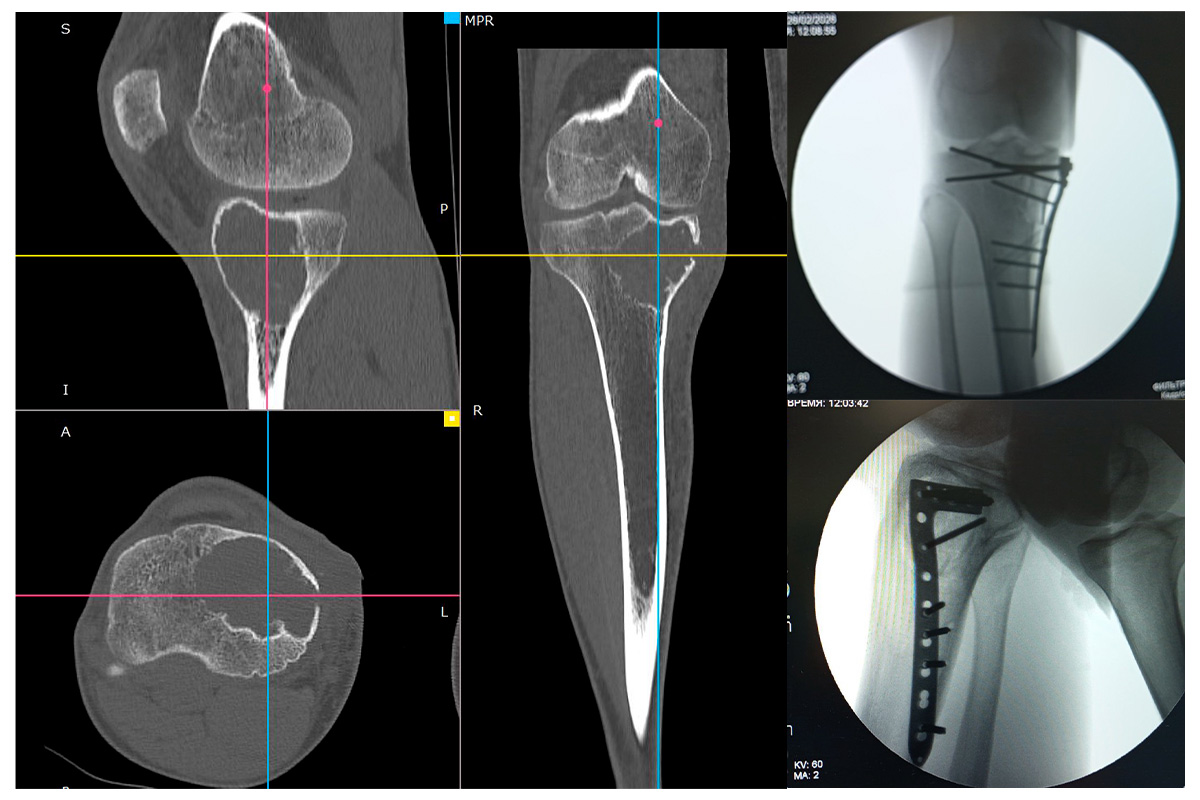

26 февраля состоялся выезд ведущего научного сотрудника лаборатории травматологии взрослого возраста РНПЦ травматологии и ортопедии, к.м.н., доцента Ситника А.А. в РНПЦ онкологии и медицинской радиологии. Совместно с заведующим отделением реконструктивной хирургии Богдаевым Ю.М. выполнено хирургическое вмешательство пациенту 29 лет с гиганто-клеточной опухолью проксимального отдела большеберцовой кости – резекция очага, пластика аллотрансплантатом, остеосинтез.